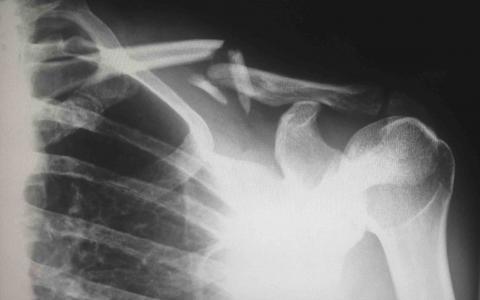

Direct force is the most typical cause of neck injuries. Since the neck is the main source of support for your skull, the neck can be easily injured by sudden head movements, overuse, and direct blows to the head or shoulder area. People who have been involved in a car accident usually suffer some sort of neck injury because they start in a still, non-moving position before their head is suddenly jolted forward or backward in a crash.